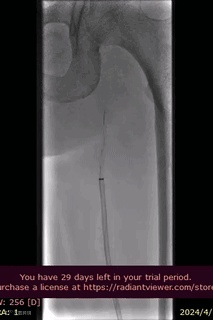

病例分享

山西省人民医院使用分享。

手术过程